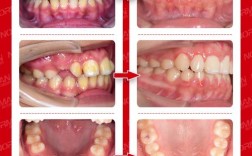

对于生长发育期的儿童,功能性矫治器可通过引导颌骨生长纠正反颌,FR-III矫治器(反向功能矫治器)通过覆盖上下牙列,刺激上颌骨向前发育,抑制下颌骨过度生长,图片中可见,佩戴矫治器6个月后,患儿下颌前突明显改善,前牙反颌解除,面型趋于正常(图1:FR-III矫治器佩戴前后对比,左侧为治疗前下颌前突,右侧为治疗后上下颌关系协调)。

固定矫治(如传统金属托槽矫正、陶瓷托槽矫正)通过施加持续矫治力,移动牙齿调整咬合,对于牙性反颌,可通过“摇椅弓”“颌间牵引”等方式将上前牙唇向移动、下前牙舌向移动;对于轻度骨性反颌,可通过拔牙为牙齿移动提供空间,图片中,固定矫治治疗前后对比可见,原本“下包上”的牙齿关系变为正常覆颌覆盖,牙列排列整齐(图2:固定矫治前后口内照,治疗前下前牙位于上前唇侧,治疗后上下前牙正常对刃)。